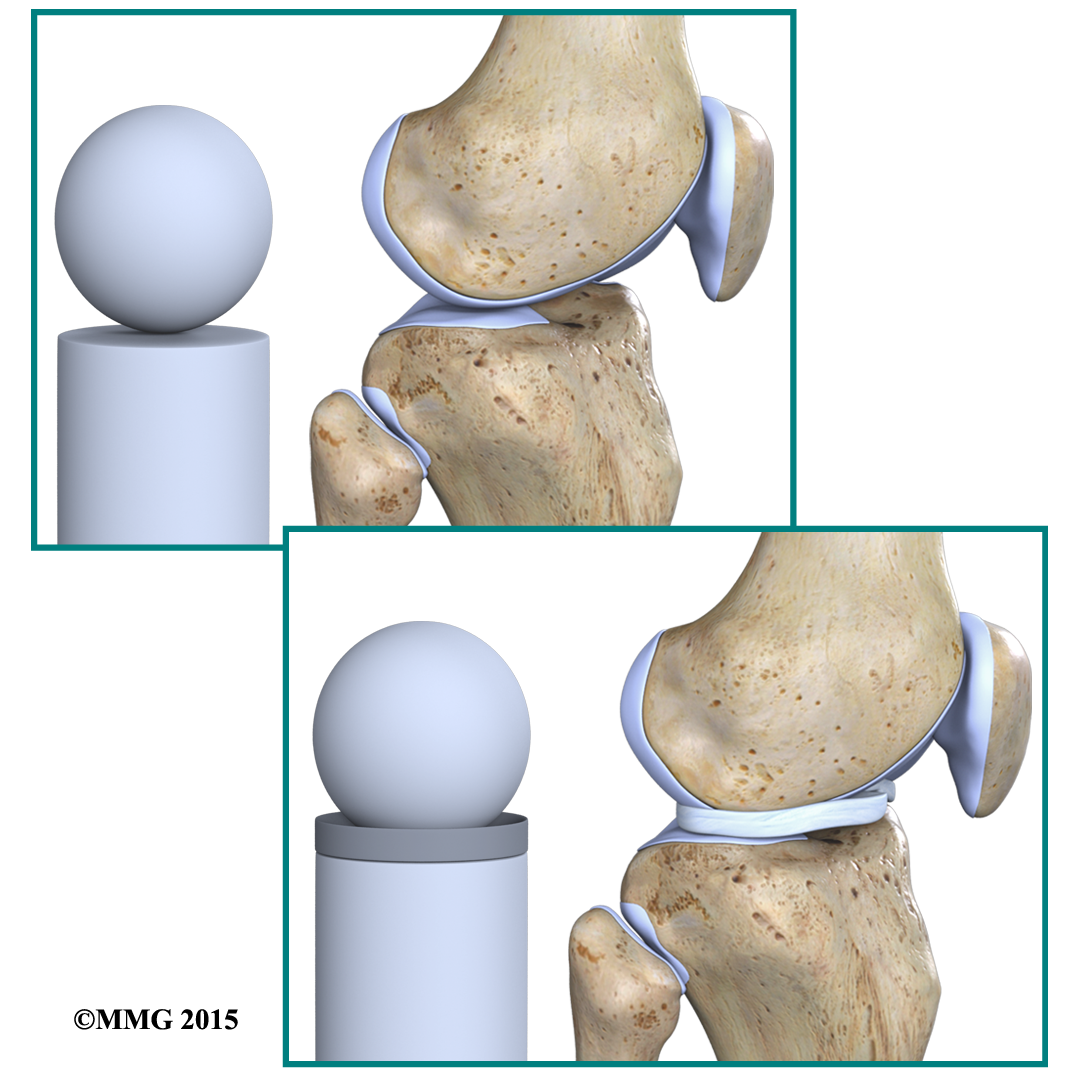

Two special types of ligaments called sit between the femur and the tibia. These structures are sometimes referred to as the cartilage of the knee, but the menisci differ from the articular cartilage that covers the surface of the joint.

Imagine the knee as a The ball is the end of the thighbone as it enters the joint, and the plate is the top of the shinbone. The menisci actually wrap around the round end of the upper bone to fill the space between it and the flat shinbone.

In addition to protecting the articular cartilage, the menisci help the ligaments with stability of the knee. The menisci make the knee joint more stable by acting like a wedge set against the bottom of a car tire. The menisci are thicker around the outside, and this thickness helps keep the round femur from rolling on the flat tibia. The menisci convert the tibial surface into a shallow socket. A socket is more stable and more efficient at transmitting the weight from the upper body than a round ball on a flat plate. The menisci enhance the stability of the knee and protect the articular cartilage from excessive concentration of force.